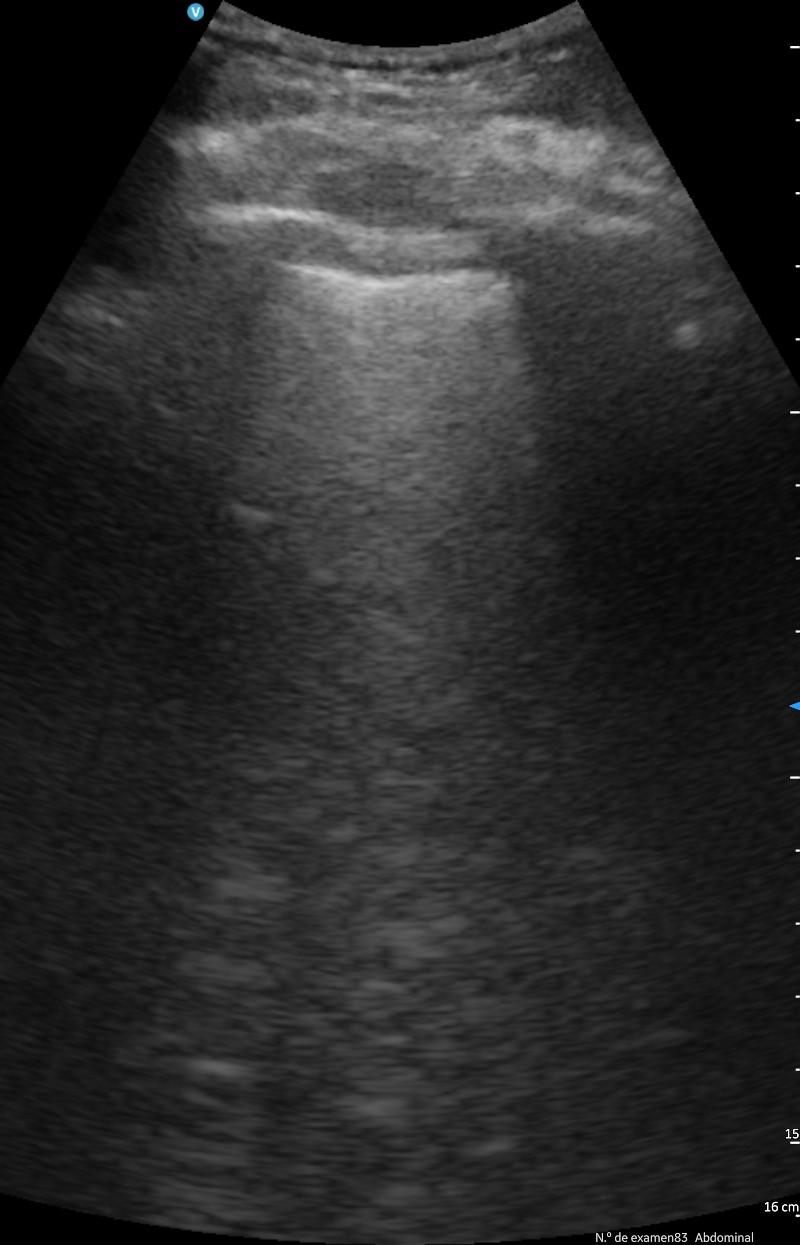

El principal uso ha sido para controlar la evolución de las insuficiencias cardíacas, controlando las líneas B, los derrames pleurales, colapso de la vena cava inferior, etc., en menores casos se ha hecho una ecocardioscopia para estimar la FEVI.

También ha sido útil en las insuficiencias respiratorias por COVID-19 o por neumonías para controlar las consolidaciones y los derrames pleurales.

La disponibilidad y uso de la ecografía portátil en el servicio de HAD ha conseguido disminuir considerablemente los traslados al hospital para realizar pruebas complementarias como: ecografías de tórax, ecografías regladas en radiología,etc. y inserción de catéteres venosos. Mejora el seguimiento de los pacientes y con ello se ajusta mejor el tratamiento y disminuyen los días de ingreso.